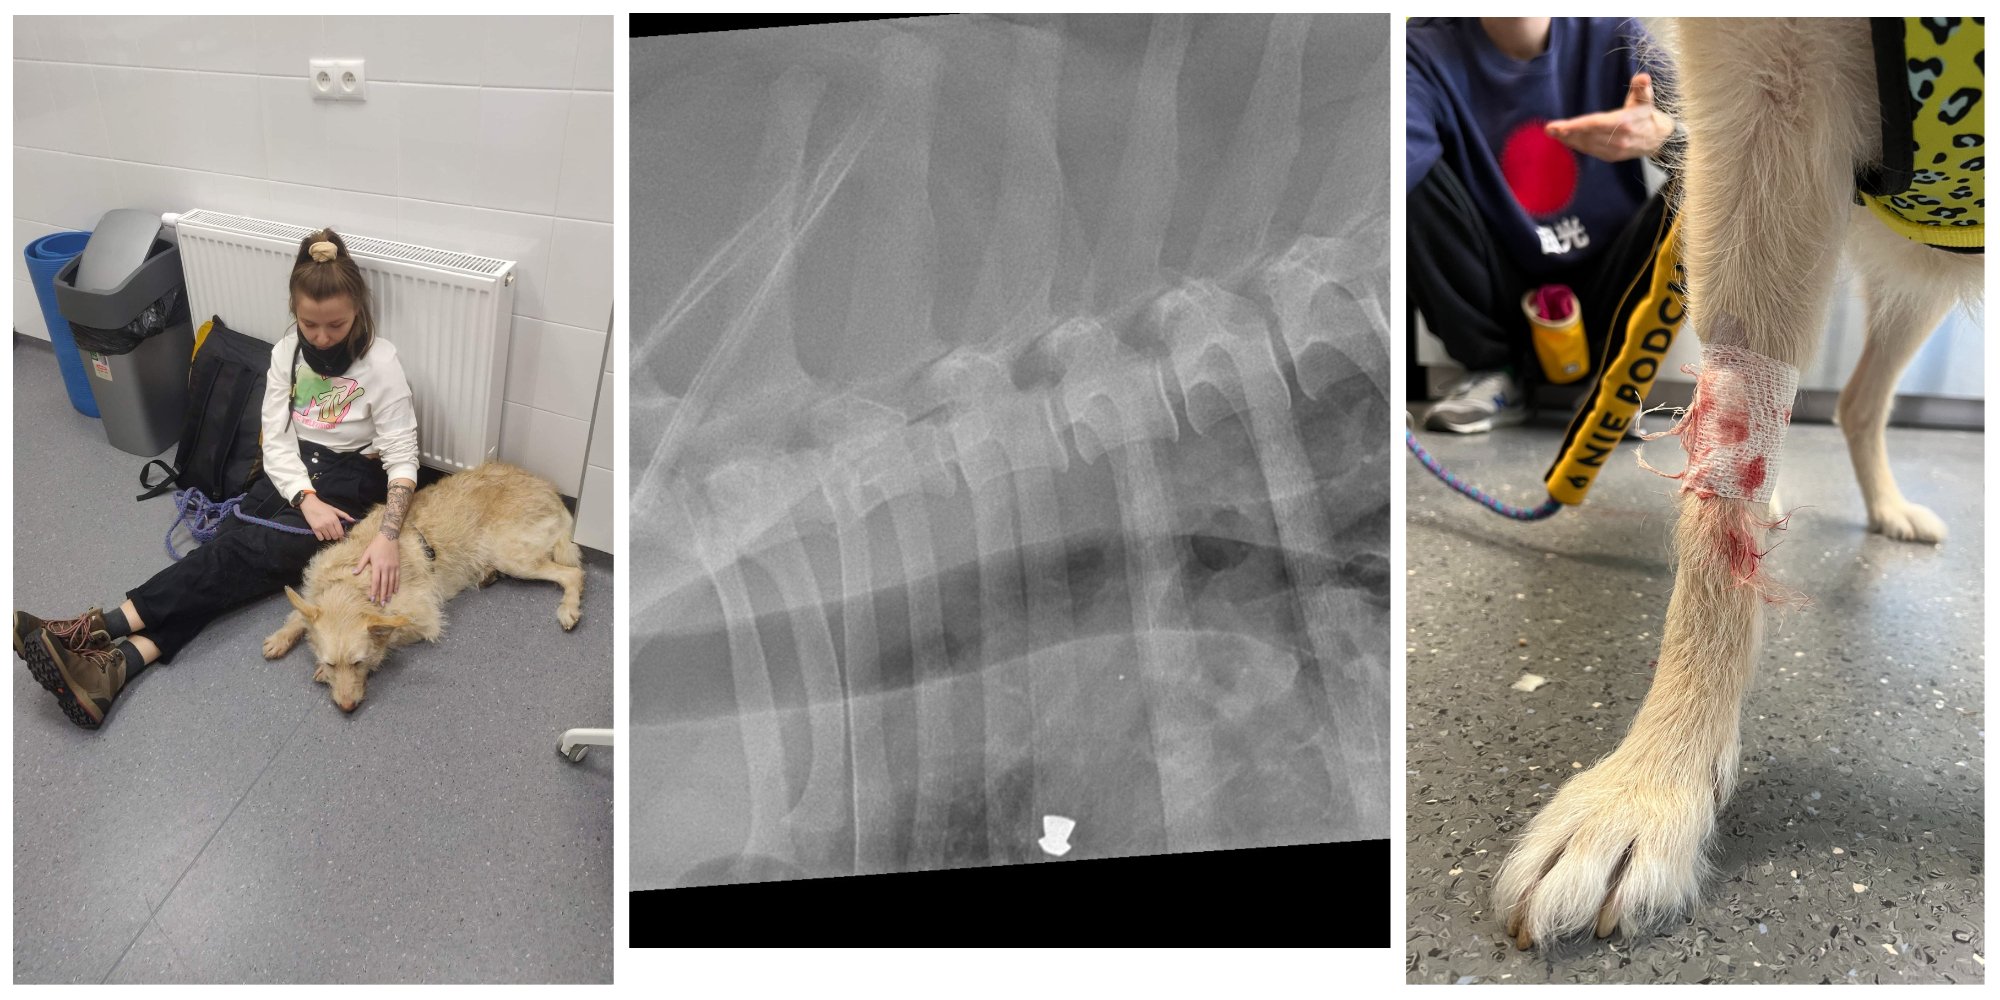

Chała jest pepsem lękowym. Nie ułatwia to przygody „chory piesek”. Jej strach wobec świata ma solidne podstawy, bo dziewczyna ma klatce piersiowej śrut, a na ciele wiele blizn, w tym jedną dużą na szyi, możliwe, że po wrośniętym łańcuchu. Boi się więc obcych, głośnych dźwięków i szybkich pojazdów, nowych miejsc, dzieci, psów, tego że stara pójdzie pod prysznic i zniknie na zawsze, ogółem wychodzenia na zewnątrz, weterynarzy, i jak my wszyscy, inflacji.

U Chały diagnostyka zaczęła się w marcu 2022, gdy nagle zaatakowała swoje odbicie w lustrze z ogromną agresją. Ponad miesiąc uparcie przebijaliśmy się przez kolejnych specjalistów i badania, aż dostaliśmy diagnozę „neościerwa”. Chałka przeszła przez to pół roku konsultacje u kilkunastu specjalistów, rezonans magnetyczny, punkcję lędźwiową, sanację jamy ustnej i ekstrakcję złamanego kła, zdjęcia RTG, wielokrotne USG jamy brzusznej i tarczycy, wymazy z uszu, niezliczone pobrania krwi, moczu i kału. Wiemy już sporo, to co możemy leczymy, ale to nie jest koniec.

Niestety leczenie samej neosporozy idzie źle. Pierwszy antybiotyk przez ponad 2 miesiące faktycznie działał, ale po nich mieliśmy nawrót. Zaostrzenie wielu objawów i pogorszenie stanu Buły. Wystrzał przeciwciał w wynikach, po których został włączony inny antybiotyk, który przez ponad 2 miesiące nie zrobił totalnie nic. Wróciliśmy do pierwszego antybiotyku, bo więcej ruchów nie ma: neosporozę leczy się dwoma rodzajami antybiotyku, oba już Buła miała podawane. Czy działa dowiemy się za dwa tygodnie. Ostatnie badanie neurologiczne Chały wykazało brak czucia powierzchniowego po lewej stronie, odruchu kroczowego po lewej i odruchu zwieracza. To poważne objawy, które zmusiły nas do szybkiej i kosztownej diagnostyki obrazowej: za 3 dni Chała będzie miała wykonane badania w narkozie: tomografię komputerową całego kręgosłupa i głowy, punkcję lędźwiową, USG i badanie laryngologiczne oraz wszystko inne czego będzie wymagała. Koszt tej imprezy to minimum 3030 zł. Następnie Chała ma termin wizyty u ortopedki, jednej z najlepszych w kraju.